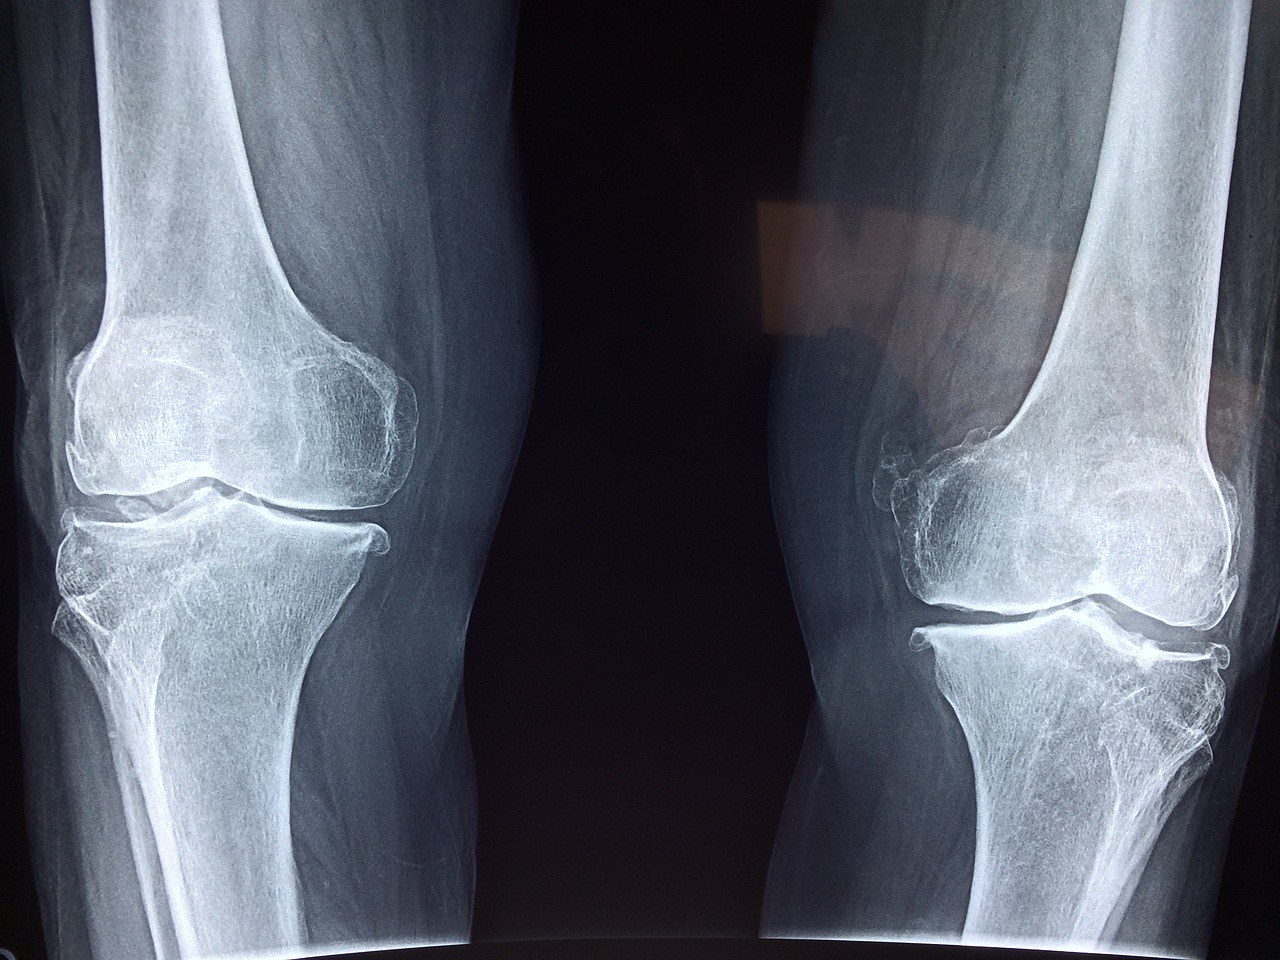

가장 대표적인 운동은 하체 근력 운동입니다. 특히, 무릎 관절을 보호하기 위해서는 허벅지 앞쪽 근육(대퇴사두근)과 뒤쪽 근육(햄스트링), 엉덩이 근육(둔근)을 강화하는 것이 중요합니다.